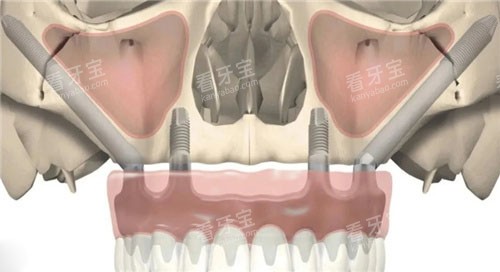

穿颧种植牙是一种将种植体穿过上颌窦底或颧骨区域,直接固定于颧骨或上颌骨的种植修复技术。与传统种植体仅植入牙槽骨不同,其核心在于利用颧骨这一人体较坚硬的骨骼(密度约为皮质骨的2倍),为种植体提供稳定的力学支撑。

颧骨位于面部两侧,呈菱形结构,骨质致密且血供丰富,抗压力强。对于上颌后牙区骨高度不足5mm的患者,传统种植体无法获得足够固位力,而穿颧种植体通过穿透上颌窦黏膜,斜向植入颧骨,可实现与天然牙相似的咀嚼功能。研究表明,穿颧种植体的10年存活率可达92%,与传统种植体相当(《口腔种植学杂志》,2023)。